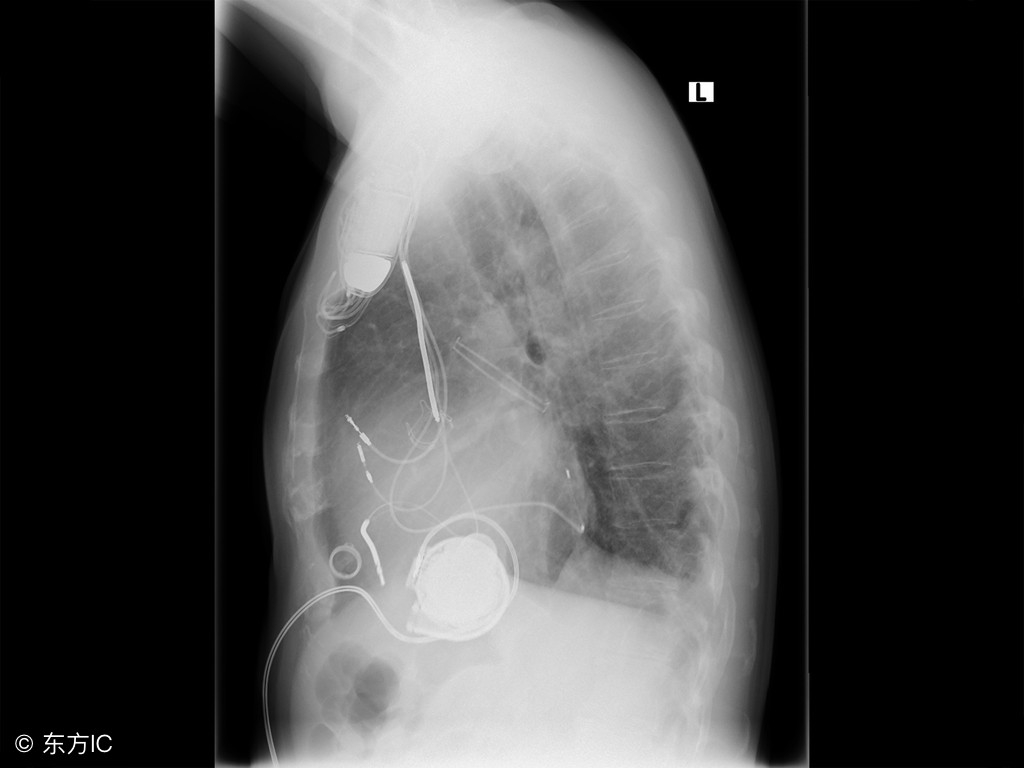

支气管扩张,是以局部支气管不可逆性解剖的异常特征为表现的,该病带来的危害非常大,患者要注意当你患有了这种疾病的时候,必须先要做出检查,检查一下病情发展到了哪一个地步,医生才好根据病情进行治疗,下面详细讲解一下支气管扩张疾病相关知识。

接下来我们来了解一下,鉴别支气管扩张的方法,因为支气管扩张会有很多的症状,所以要想辨别清楚,也是比较困难的,今天我们就来了解一下,如果是慢性支气管炎的话,大部分会出现在中年以上的患者,冬春季节会出现咳嗽,咳痰,还会伴有喘息,多为白色粘液痰,而且发生感染的时候会有浓痰。那么除了这之外,肺结核就会表现出低热,盗汗,全身无力,消瘦等症状,所以每一种症状的不同或是疾病的不同,表现方法又会有所不同,治疗起来也就会不同。